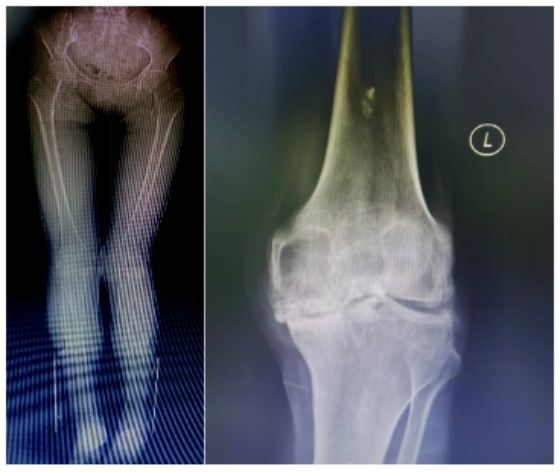

53 岁的平女士多年来一直被膝关节疼痛所困扰,近来疼痛加重,影响正常直立行走,遂找到王文波求治。王文波检查发现患者存在严重的双侧弓形股骨,无法进行髓内定位,常规膝关节置换方式无法完成手术,决定采用便携式导航定位技术,采用术中髓外定位方式,为平女士精准定位截骨完成全膝关节置换手术。